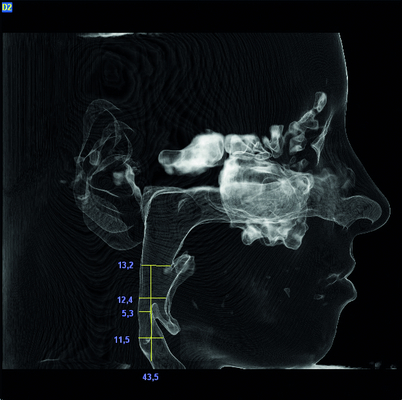

- Digitale Vermessung der oberen Luftwege

Mittels Zahnschiene (Protrusionsschiene) besteht die Möglichkeit, einen positiven Effekt der Unterkiefervorverlagerung zu testen und ggf. das Ausmaß der notwendigen Verlagerung festzustellen.

Durch eine Umstellungsosteotomie mit Kiefervorverlagerung (oft Ober- und Unterkiefer gemeinsam) kann das Krankheitsbild dann ursächlich behandelt werden.